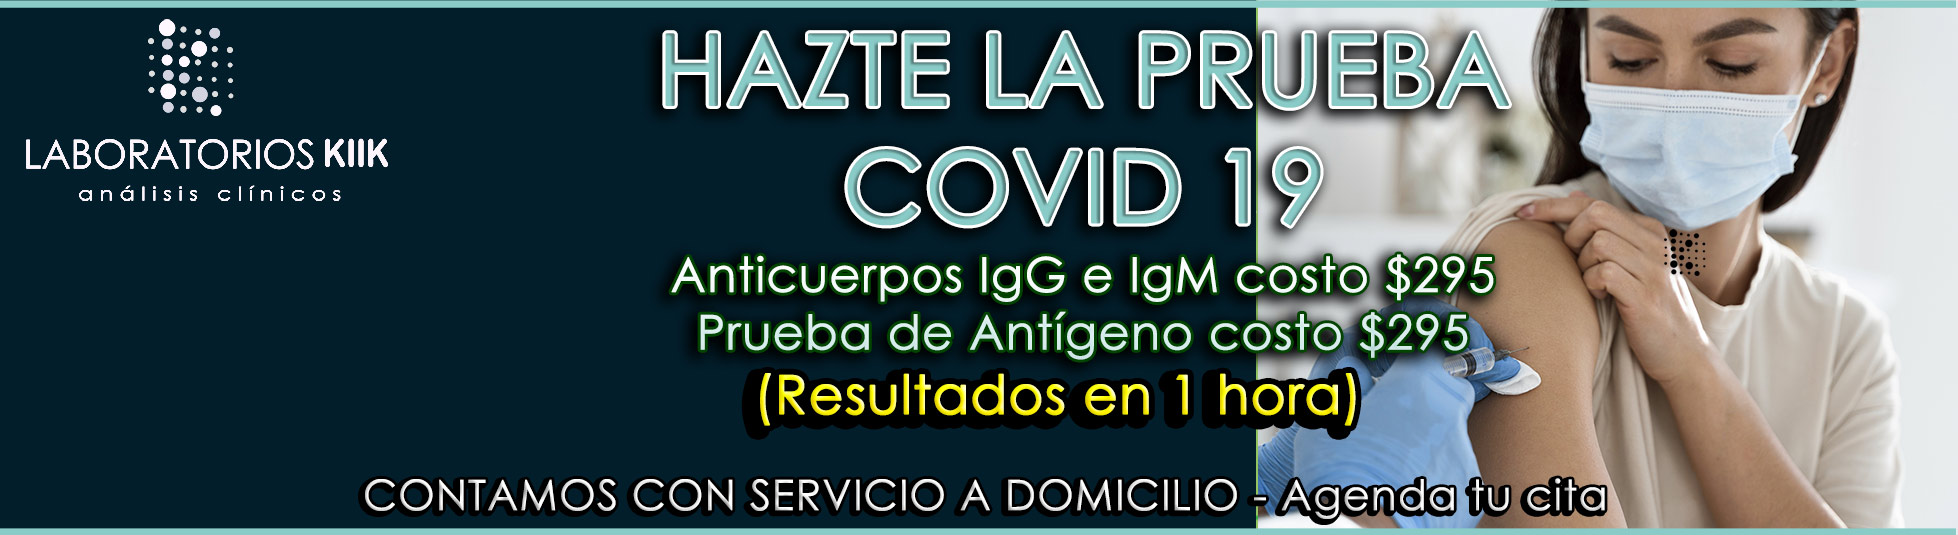

Por tiempo indefinido contamos con un 30% de descuento en todos nuestros estudios (excepto promocionales) y por introducción el servicio “No salgas de casa, nosotros vamos hacia ti” sin ningún costo extra.

- Prolongación Reforma No. 4906 Local E. Col. La Libertad. Puebla, Pue.

- (222) 977 23 33

- 22 15 28 00 00